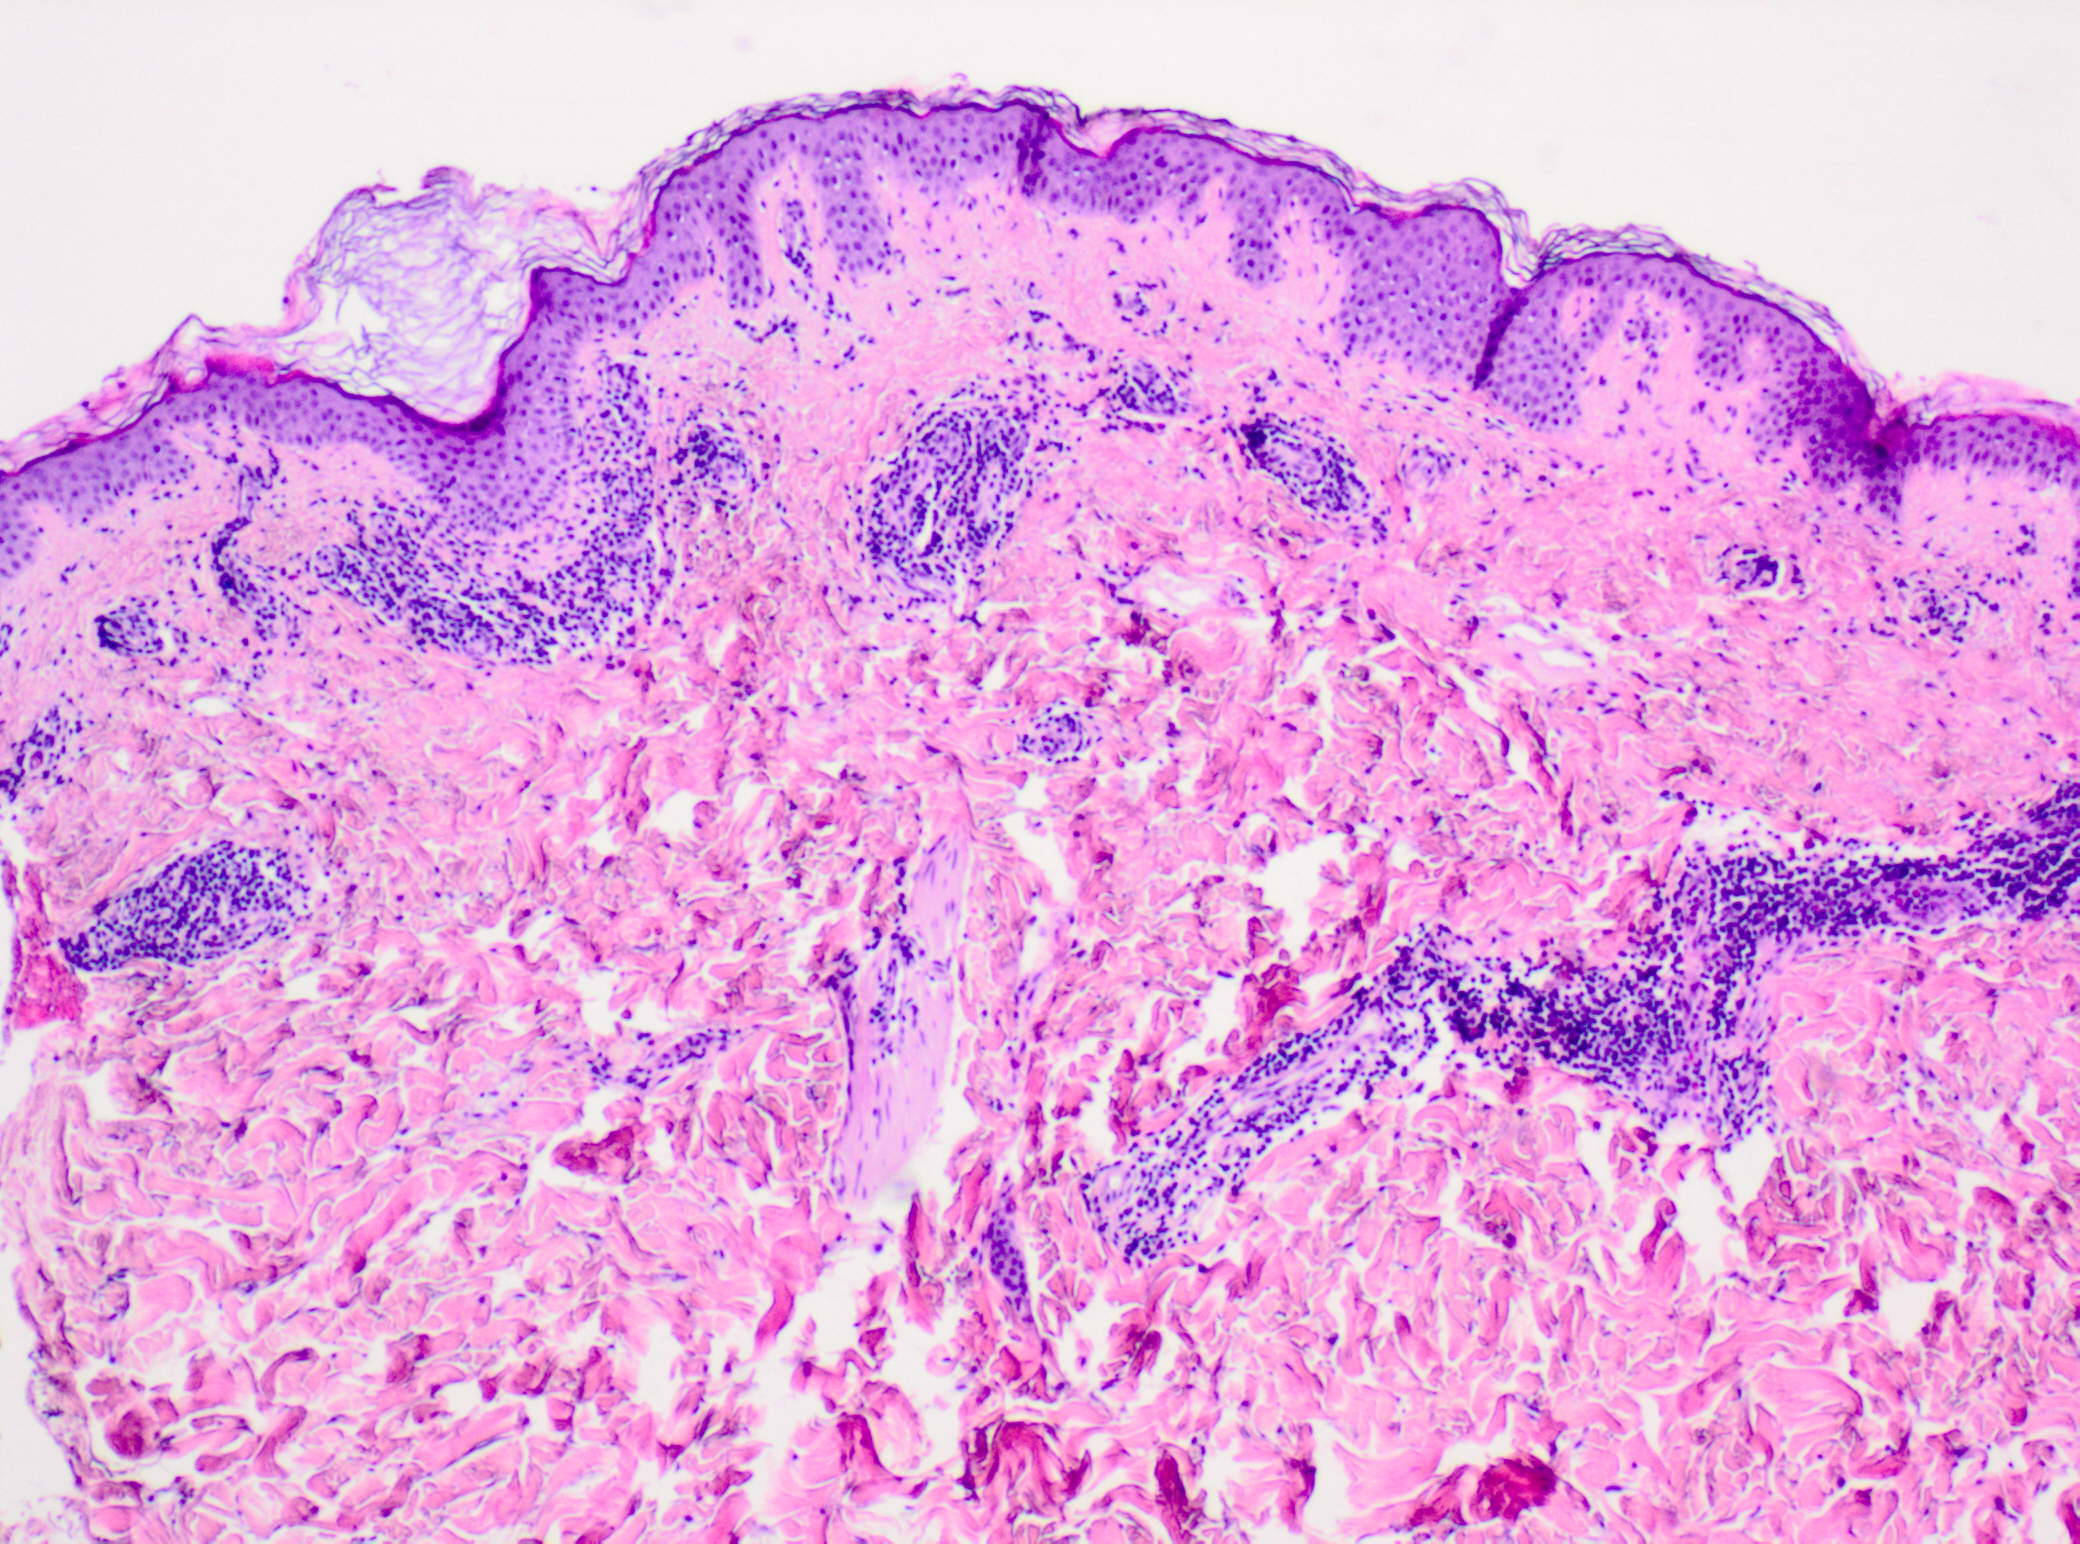

L’intensità del quadro clinico e della sintomatologia, ben oltre un semplice prurito, (si avvicinava al dolore), ci ha indotto ad eseguire prontamente una biopsia di un elemento, per trovare conferma alla nostra ipotesi diagnostica. L’esa me istologico con un infiltrato perivascolare di linfociti ed eosinofili a varia densità, ha confermato l’ipotesi diagnostica.

Di seguito le immagini istopatologiche.

Ematossilina-Eosina 2 x Infiltrato superficiale perivascolare e interstiziale di eosinofili e linfociti

Ematossilina Eosina 4x Infiltrato superficiale perivascolare e interstiziale di eosinofili e linfociti